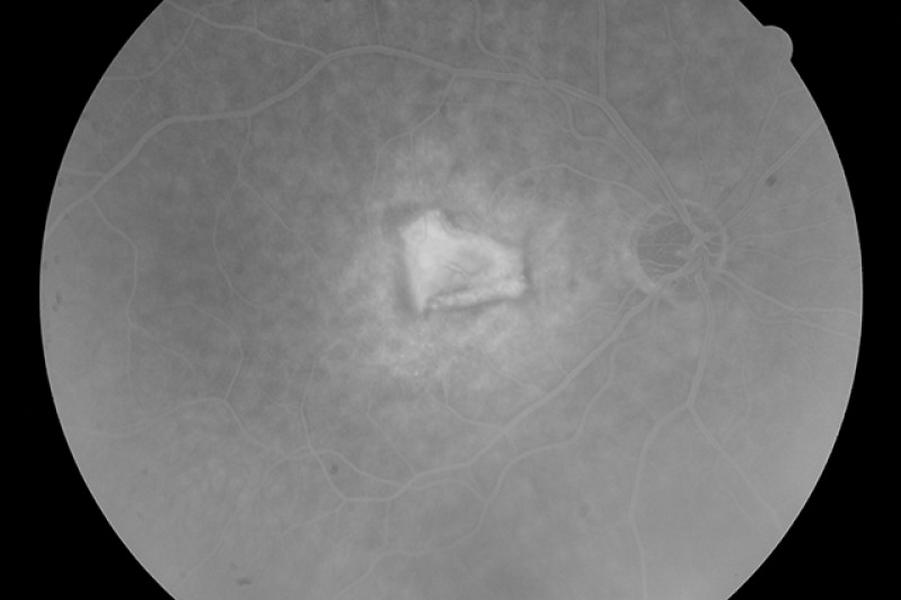

Η ψηφιακή φλουοραγγειογραφία είναι μια απεικονιστική οφθαλμολογική εξέταση για τη μελέτη του οπισθίου τμήματος του οφθαλμού (βυθός).

Πραγματοποιείται στο ιατρείο με έγχυση μιας σκιαγραφικής ουσίας στη φλέβα και στη συνέχεια τη λήψη διαδοχικών φωτογραφιών που απεικονίζουν την κυκλοφορία του αίματος στον αμφιβληστροειδή.

Η ψηφιακή φλουοραγγειογραφία χρησιμοποιείται για τη διάγνωση και παρακολούθηση μιας πληθώρας αγγειακών παθήσεων του αμφιβληστροειδούς και του χοριοειδούς. Οι πιο γνωστές από αυτές είναι η υγρά μορφή της ηλικιακής εκφύλισης της ωχράς κηλίδας, η διαβητική αμφιβληστροειδοπάθεια και οι αγγειακές αποφράξεις του αμφιβληστροειδούς.